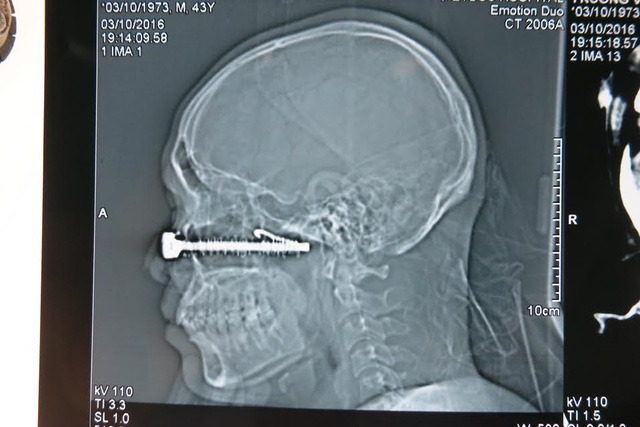

VBF-Mới đây tập thể y bác sĩ VN đã mổ cấp cứu thành công 1 bệnh nhân đang trong tình trạng nguy kịch tại bệnh viện Việt Đức. Theo đó nạn nhân đã bị 1 đinh sắt dài 10cm đâm thẳng vào vùng mắt sau khi bị ngã xe. Ca mổ đã diễn ra xuyên đêm và thành công tốt đẹp.Tai nạn trong chớp mắt đã khiến một chiếc đinh vít (kèm móc sắt) dài tới hơn10 cm găm xuyên qua mặt một người đàn ông sát ngay dưới một bên mắt. Một cuộc hội chẩn liên viện giữa bệnh viện (BV) Việt Đức và BV Mắt Trung ương nhanh chóng diễn ra tại BV Việt Đức sau khi tiếp nhận bệnh nhân.

Một ca mổ cấp cứu trong đêm có đầy đủ các chuyên khoa: Phẫu thuật tạo hình hàm mặt, Thần kinh, Mạch máu, Mắt, Gây mê hồi sức... tiến hành lấy bỏ chiếc đinh vít khủng khiếp đâm sâu gần 10 cm ra khỏi khuôn mặt bệnh nhân.

Nhìn lại dị vật đã găm sâu vào mặt bệnh nhân Trương Văn T. 43 tuổi (Tuyên Quang) lúc đó chúng tôi không khỏi rùng mình. Đó là một chiếc đinh vít cỡ cực đại có các vòng lò xo xoắn xung quanh thân kèm móc sắt uốn cong như lưỡi câu ở phía đầu.

TS. BS. Nguyễn Hồng Hà, Trưởng khoa Phẫu thuật tạo hình hàm mặt BV Việt Đức cho biết:"Nhìn phim chụp từ BV tỉnh cho thấy tổn thương rất phức tạp, nên khi tiếp nhận các bác sĩ khẩn trương đặt các đường ven truyền, hồi sức, giảm đau cho BN và chụp lại phimcắt lớp. Trên phim CT cho thấy vị trí của đầu đinh vít gần chạm vào nền sọ (chưa xuyên vào trong não) và các mạch máu lớn.Tuy nhiên đứng trước ca mổ như vậy, các bác sĩ phải hội chẩn chuẩn bị hết sức kỹ càng, các biện pháp dự phòng tối ưu nhất được đề ra".Cuộc hội chẩn liên viện, liên khoa: phẫu thuật tạo hình,mắt (bác sĩ bệnh viện Mắt Trung ương), mạch máu (dự phòng khâu nối mạch máu rách), thần kinh (dự phòng trường hợp có huyết khối trong mạch cảnh phải mở hộp sọ để xử trí), gây mê hồi sức diễn ra lúc 22h ngày 3/10/2016 tại BV Việt Đức.

22h30 phút, ThS. BS. Vũ Trung Trực, khoa Phẫu Thuật tạo hình - hàm mặt phối hợp cùng kíp phẫu thuật, gây mê hồi sức kiểm soát huyết áp của bệnh nhân (để giảm nguy cơ mất máu trong trường hợp có tổn thương mạch), sau đó tiến hành mở rộng vết thương. Đinh đâm xuyên từ thành trước đến thành sau của xoang hàm, vào hố chân bướm hàm (giữa xương bướm và xoang hàm phía sau) là vùng liên quan đến các tổ chức thần kinh, mạch máu từ tim lên não và từ trên não xuống; gần chạm vào động mạch cảnh (là động mạch rất lớn đi từ tim xuyên qua vùng chân bướm hàm lên nuôi não), cách động mạch cảnh 5 mm (rất may chưa tổn thương đến mạch cảnh).

Đinh đâm sâu toàn bộ xương mặt, đến tận nền sọ, móc câu sắt trên đinh ngoắc vào sâu trong xương mặt cùng với lò xo xung quanh nên rất khó rút ra.Vỡ toàn bộ sàn ổ mắt, vỡ xương thành trước hốc mắt và tổn thương cực dưới của nhãn cầu.

Các bác sĩ chuyên khoa Mắt cố gắng bảo tồn mắt cho bệnh nhân nhưng do có các vòng lò xo xoắn trên đinh vít đã làm dập nát cả cực dưới của nhãn cầu nên không thể bảo tồn con mắt phải, bắt buộc phải múc bỏ nhãn cầu. Tuy nhiên cũng may là bệnh nhân chỉ chảy máu vừa và máu tụ ở xoang hàm, trong quá trình lấy bỏ đinh không bị tình trạng chảy máu ồ ạt do tổn thương mạch máu.Các bác sĩ tiến hành khâu nối, tạo hình lại các tổn thương của sàn hốc mắt, các vết thương trên vùng mặt. Ca mổ kết thúc lúc 4h sáng ngày 4/10.

ThS. BS. Vũ Trung Trực cho biết: “Sau mổ chụp lại toàn bộ hệ thống mạch cảnh 2 bên cổ, nền sọ cho thấy hệ mạch cảnh không bị tổn thương. Bệnh nhân không sốt, đã nói chuyện, ăn uống được và đang điều trị kháng sinh chống nhiễm khuẩn. Bệnh nhân sẽ được xem xét chuyển BV Mắt để lắp đặt mắt giả tùy vào tiến triển của vết thương”.Các bác sĩ khuyến cáo: Với những trường hợp như vậy tuyệt đối không được rút dị vật ra, chỉ làm mọi cách để cầm máu (thấm gạc, băng ép). Nếu rút ra phải được đánh giá bởi chuyên gia y tế. Với những tổn thương đâm sâu vào phần nền sọ phải phối hợp đa chuyên khoa về phẫu thuật hàm mặt tạo hình, thần kinh, mạch máu, mắt, tai mũi họng...